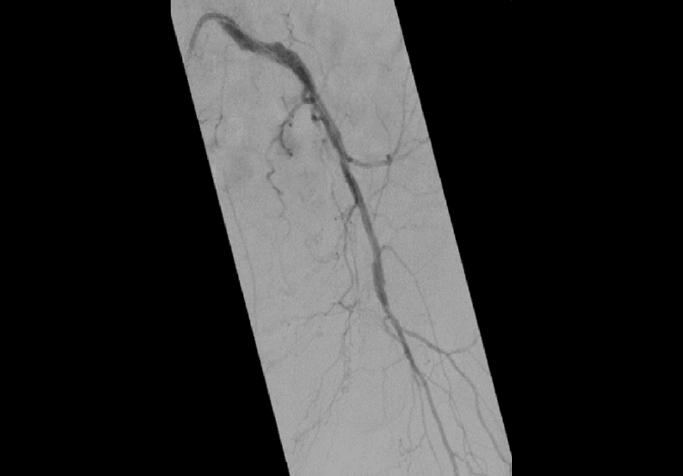

Em procedimentos minimamente invasivos, onde a anatomia pode mudar a cada movimento e as decisões precisam ser tomadas instantaneamente, a capacidade de trabalhar com segurança, rapidez e confiança faz a diferença entre um procedimento eficiente e um repleto de imprevistos.